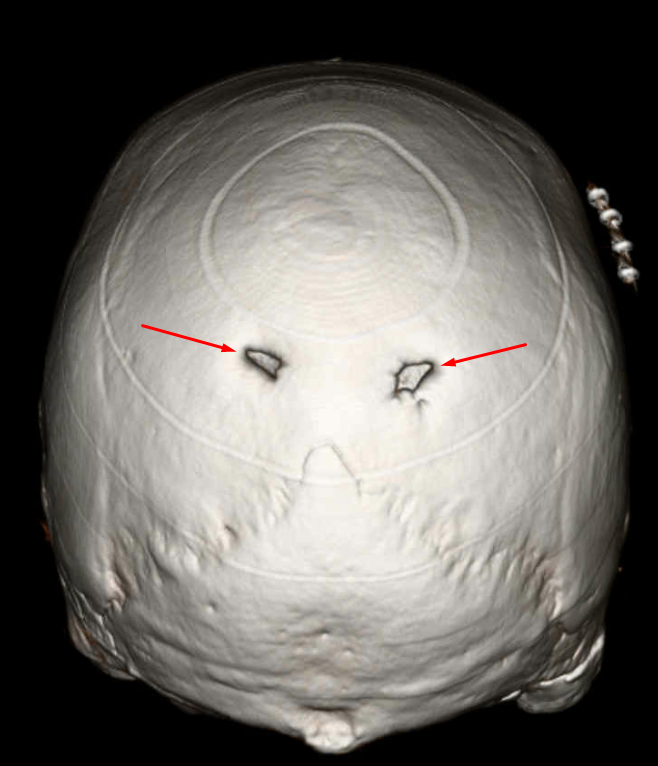

Age: 46

Sex: Male

Indication: Scalp Wound